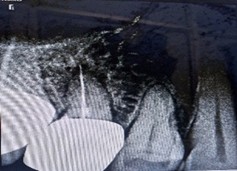

Despite a guarded prognosis for tooth survival, we performed thorough canal disinfection and placed Metapex as an intracanal medicament for four weeks. The patient reported no inter-appointment discomfort. At the subsequent visit, radiographs confirmed complete resolution of the periapical lesion, and root canal obturation was successfully completed.

Figure 2: Metapex placement after thorough canal disinfection. Figure 3: Post 4 weeks, complete resolution of periapical lesion.

Figure 3: Post 4 weeks, complete resolution of periapical lesion. Figure 4: Post obturation IOPA after 4 weeks.